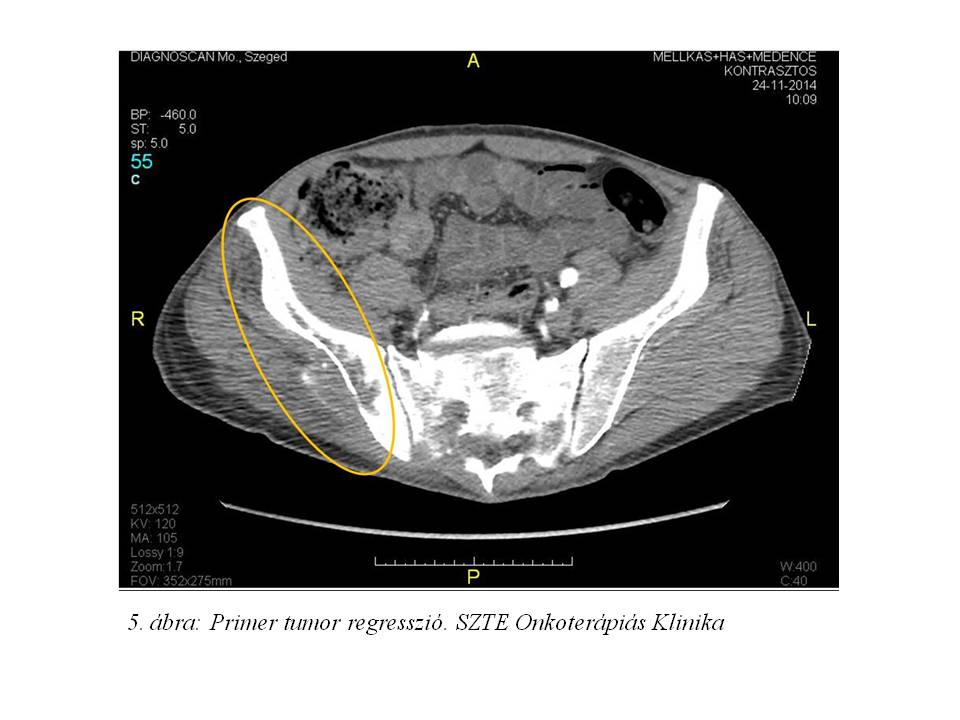

Ezt követően re-staging mellkas-, has-, kismedence-CT és angiográfia történt (2014.11.24., 5. ábra). Pulmonalis metasztázis továbbra sem volt igazolható. A gluteális tumor komplett remisszóba került, csupán a lytikus csontfolyamat engedett következtetni a korábbi daganat meglétére.